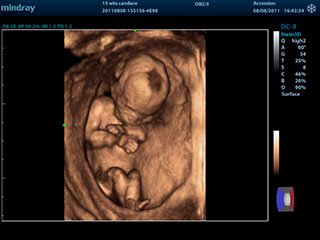

3D/4D УЗИ при беременности

4D УЗИ дает возможность разглядеть мельчайшие детали строения, например, пол ребенка, количество пальчиков на ручках и ножках. Если проводить 4 d диагностику на 32 неделе беременности, то можно увидеть мимику ребенка, как он улыбается или хмурится.